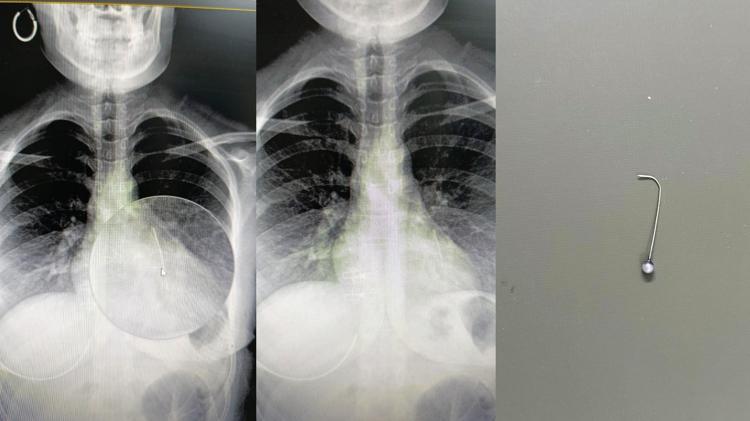

Olay, Günbalı Mahallesi’nde meydana geldi. Evden dışarı çıkmaya hazırlanan Bedia Özbay, eşarbını düzeltmek isterken ağzında tuttuğu toplu iğneyi yuttu. Nefes almakta zorlanan Özbay, ailesi tarafından Mehmet Akif İnan Eğitim ve Araştırma Hastanesi’ne götürüldü. Yapılan tetkiklerde iğnenin Özbay'ın sol akciğerine saplandığı tespit edildi.

Hayati tehlikesi bulunan Bedia Özbay, Op. Dr. Mehmet Emin Balcıoğlu tarafından ameliyata alındı. Balcıoğlu, bronkoskopi yöntemiyle sol akciğerdeki iğneyi operasyonla çıkardı. Yaklaşık bir saat süren ameliyatın ardından Özbay’ın hayati tehlikeyi atlattığı belirtildi.

Op. Dr. Balcıoğlu, operasyon sonrası yaptığı açıklamada, “16 yaşındaki hastamız, öğle saatlerinde başörtüsünü düzeltirken toplu iğneyi yutmuş. Öğlenden beri Şanlıurfa Devlet Hastanesi’nde bekliyormuş. Şanlıurfa ve çevre illerdeki hastaneler hastayı kabul etmemiş. Bronkoskopi yöntemiyle sol akciğerin alt kısmına yerleşmiş iğneyi çok şükür başarıyla çıkardık. Hastamızın durumu iyi, birkaç gün misafir ettikten sonra sağlıklı şekilde evine göndereceğiz” dedi.